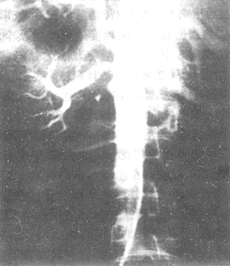

图1 腹主-肾动脉造影显示右肾动脉闭塞,左肾动脉狭窄

图2 腹主-肾动脉造影显示节段狭窄型腹主动脉炎并发肾动脉狭窄

图3 腹主-肾动脉造影显示闭塞型腹主动脉炎并发肾动脉狭窄

图4 腹主-肾动脉造影显示膨胀型腹主动脉炎并发肾动脉狭窄